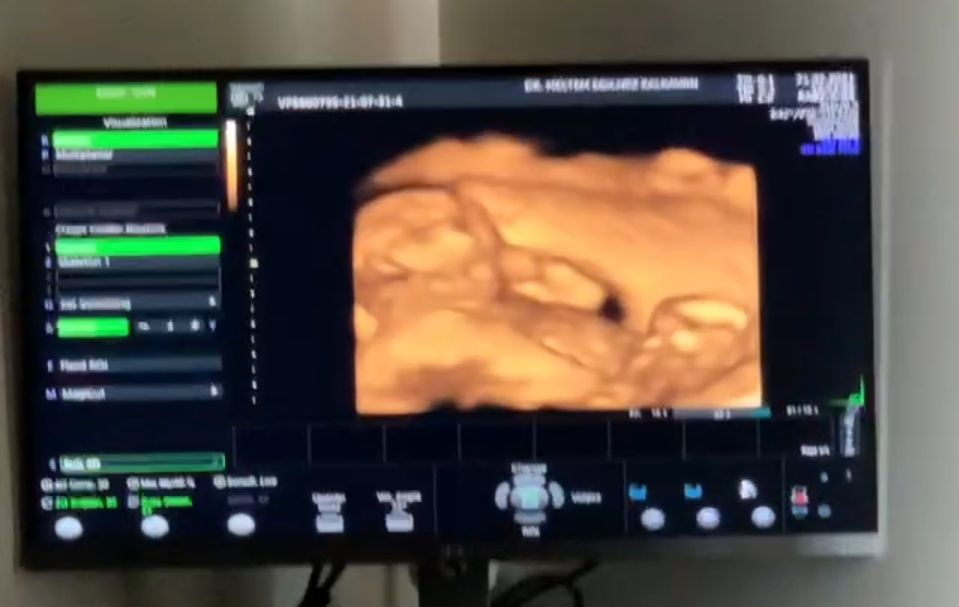

Сегодня были наконец-то на узи🤗😍🤪😊

Я так рада. Что ребеночек здоров, что все в порядке с ним. Показывала 3Д) такой хорошенький. Прям человечек.

Лежит себе на спине, глазки трет.